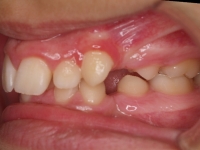

La paciente O.O. acude a nuestra consulta por:

– Canino 13 e incisivo lateral 42 en posición ectópica.

– Canino 23 incluido.

Con lo que decide realizarse un tratamiento de ortodoncia de duración de 24 meses con brackets damon Q.

CASO COMPLETO: